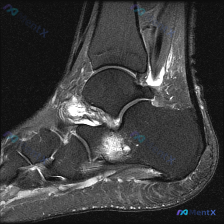

怀疑踝关节软组织积液但MRI单层面正常?这个分析思路值得参考

本次分析对象为踝关节MRI-T2序列-轴位单一扫描层面,患者主诉怀疑存在软组织积液,要求对影像进行评估。

- 解剖结构层面:该层面位于踝关节上方,可显示胫骨远端、腓骨远端及胫腓联合区域

- 骨骼结构:骨皮质信号正常,骨髓腔无明显不均匀高信号,排除急性骨髓水肿;胫腓关节间隙可见

- 韧带结构:下胫腓联合前后韧带走行正常,呈条状低信号,无增粗、肿胀或高信号改变,结构相对完整

- 肌腱结构:腓骨长短肌腱、胫骨后肌腱/趾长屈踇长屈肌腱、跟腱走行正常,形态信号均正常,腱鞘无明显增宽

- 异常排查:未见占位性病变、急性骨挫伤、严重肌腱炎或韧带损伤的典型高信号,软组织层面无异常肿胀